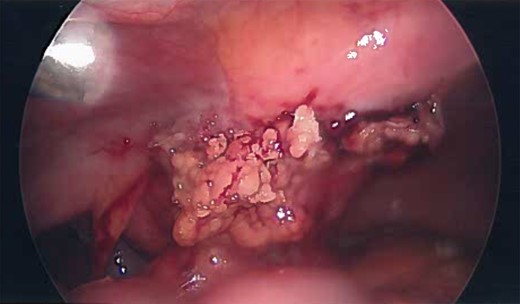

Patient was administered general anesthesia with placement of endotracheal tube. She was placed in lithotomy position (stirrups), both arms tucked at sides, strap secure across chest and a bair hugger (warmer) was placed around upper chest/head/neck area. Our patient was prepped with betadine for a vaginal/perineal prep and chloroprep was used on the abdomen. After sterile draping of the patient, and official time-out with all in agreeance, the Urologist evaluated the bladder with a cystoscopy using a 70° scope to survey for any persistent urachal abnormalities, and confirmed that no fistula/congenital abnormalities from inside bladder. General Surgeon scrubbed in and proceeded with insertion of veress needle and insufflated the abdominal cavity with CO2. Once the abdominal pressure reached 15 mmHg, General Surgeon used a 5 mm/0° laparoscope inside a 5 mm first-entry trocar and watched himself insert the trocar through each layer until passing through the peritoneum and into the abdominal cavity. Two 8 mm robotic Xi trocars were inserted, a 12 mm AirSeal Assistant port, and the 5 mm first entry port was replaced with a third robotic 8 mm cannula. Altogether 3–8 mm robotic ports, a 12 mm assistant port, and a 30° robotic scope was utilized during the case. Docking of the robot followed port placement with ‘renal right’ selected on the patient cart while the patient was placed in slight Trendelenburg. Da Vinci Xi instruments used were a fenestrated bipolar and a monopolar scissor to begin dissection. Initial survey of abdomen confirmed that there is an extension of a structure from the dome of the bladder to the posterior surface of the umbilicus (Fig. 4) and more suggestive of an infected urachal cyst. Further evaluations revealed that the cyst surrounding the umbilicus is inflamed and had multiple pus filled cavities. A complete resection of the cyst and the connecting structure was resected by Da Vinci Xi robotic system (Fig. 5). The bladder was filled with 300 ml of sterile normal saline mixed with methylene blue dye through the Foley catheter to determine any bladder otomies from the dissection. None were present. Urologist over sewed a thin area of the bladder with a 3-0 vicryl SH suture (Fig. 6). Complete resection of the cyst was performed successfully (Fig. 8). Slight irrigation was used to check for bleeding and the specimen was put in an endocatch bag to be retrieved when ports are ready for removal. A 19 Fr Blake drain was placed in the abdominal cavity and secured with a 2-0 nylon suture. Foley catheter is also indwelling.

Inflamed and necrotic appearance of the urachal cyst with multiple pus filled cavities.